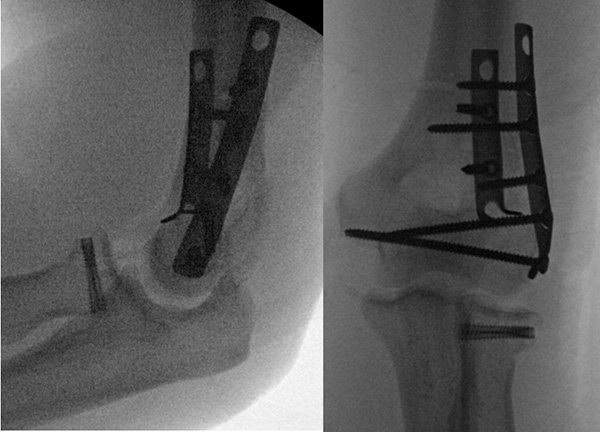

Intra-operative views of radial head screws (note also the plates on the associated distal humerus fracture)

Intra-operative x-ray of a radial head replacement for an un-reconstructable radial head fracture.